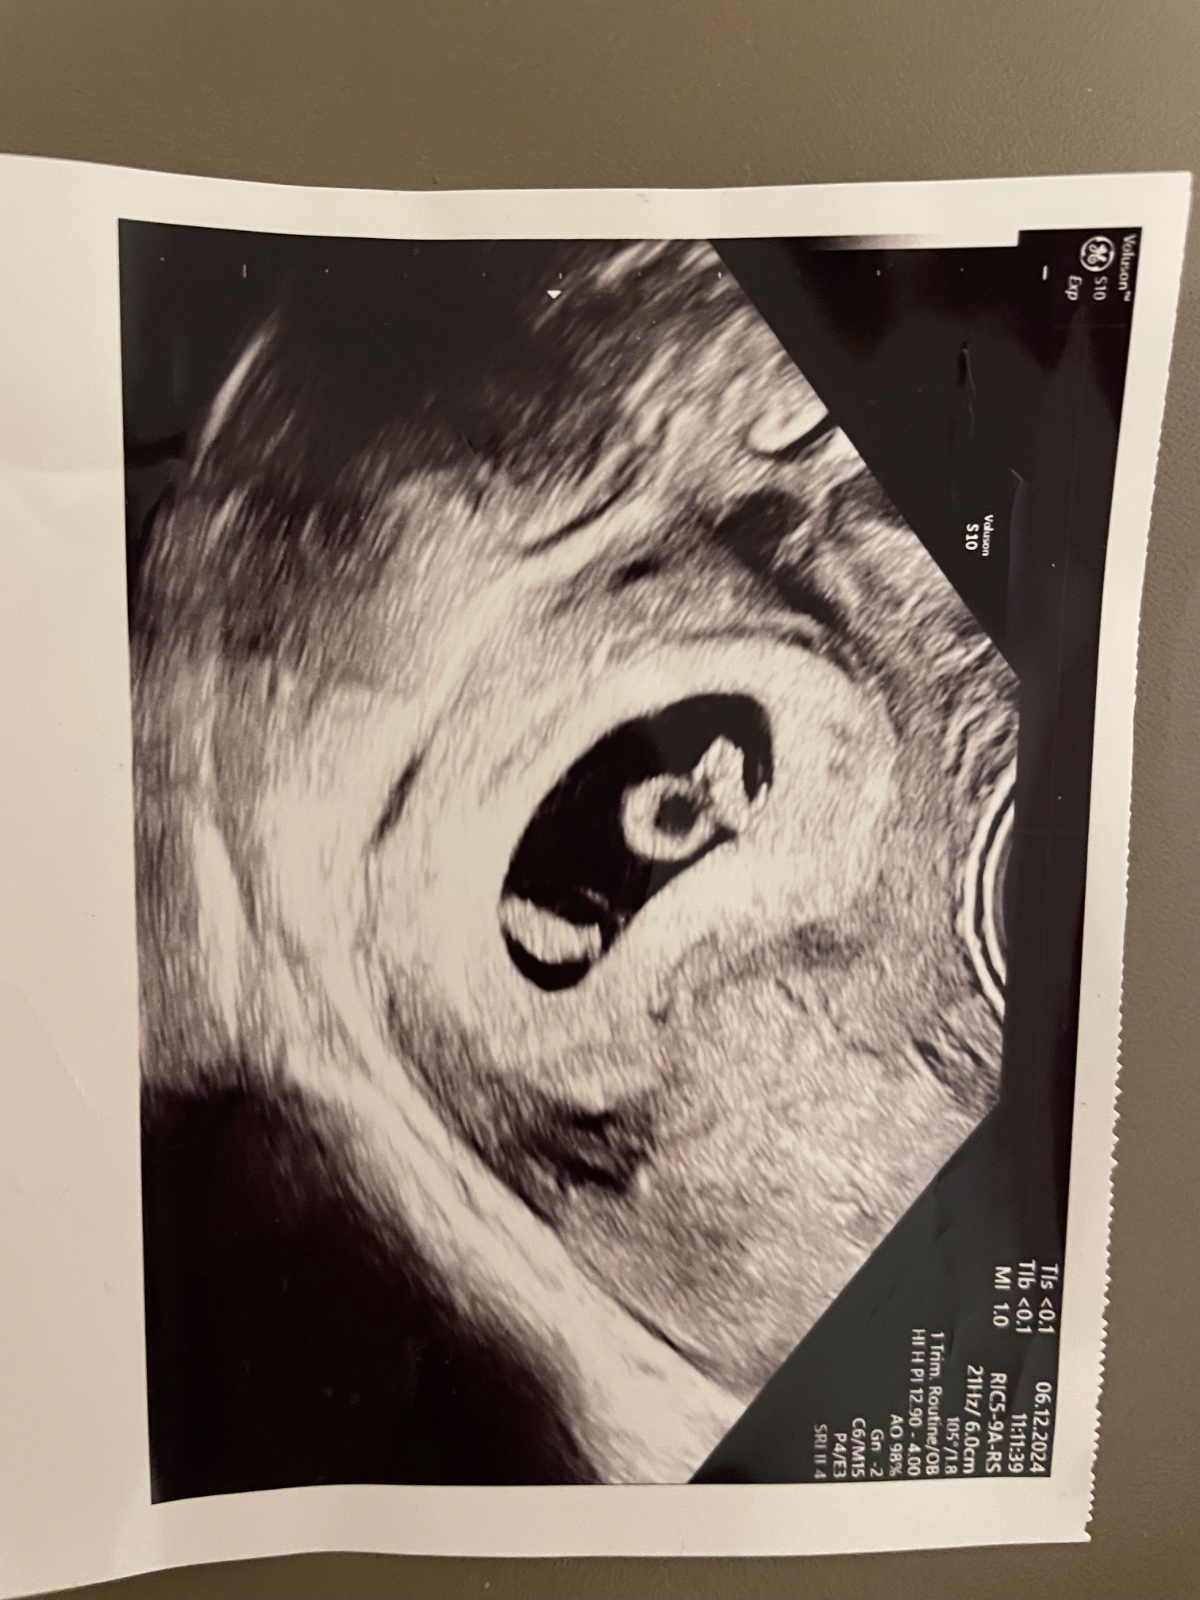

@cecilia29 som 6+4tt su tam 2 akcie 😔 o tyzden kontrola, ci obe biju…jedno je o trosku menšie

@cecilia29 ahoj, tak konfety doma nestrieľamr, ale už sme sa dali do kludu obaja, teda hlavne manžel. Bral to prvy týždeň veeelmi tragicky, no paradoxne keď som mu povedala, že tam sú nakoniec 2 tak zmenil rétoriku a úplne zmäkol z minuty na minútu. Nečakala som to, ani on, ale keď som mu to celé ukázala na YouTube ako sa taká interupcia robi a ako aktuálne vyzerajú nasi dvaja v bruchu tak mu doslo zo seba zle, že to odomna chcel. On mal predstavu že mi dajú injekciu a ja dostanem menštruáciu a je po vsetkom … boli to veľmi silne dni posledné týždne, ale našťastie ho osvietilo a postavil sa k tomu ako chlap. Aj keď mu to trvalo, no mala väčšina žien pravdu, že reagoval v afekte a chcelo to čas 🍀

@ahhola áno a na ultrazvuku fotke mam čas 11:11 🙈